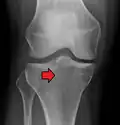

Lipohemarthrosis (presence of fat and blood from bone marrow in the joint space after an intraarticular fracture) seen on X-ray in a person with a subtle tibial plateau fracture -

Subtle tibial plateau fracture on an AP X ray of the knee -

A tibial plateau fracture seen on X-ray